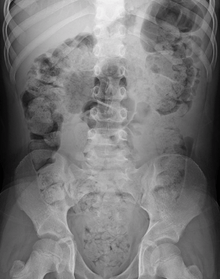

During physical examination, scybala[24] (manually palpable lumps of stool) may be detected on palpation of the abdomen. Rectal examination gives an impression of the anal sphincter tone and whether the lower rectum contains any feces or not. Rectal examination also gives information on the consistency of the stool, the presence of hemorrhoids, admixture of blood and whether any tumors, polyps or abnormalities are present. Physical examination may be done manually by the physician, or by using a colonoscope. X-rays of the abdomen, generally only performed if bowel obstruction is suspected, may reveal extensive impacted fecal matter in the colon, and confirm or rule out other causes of similar symptoms.[7][8]